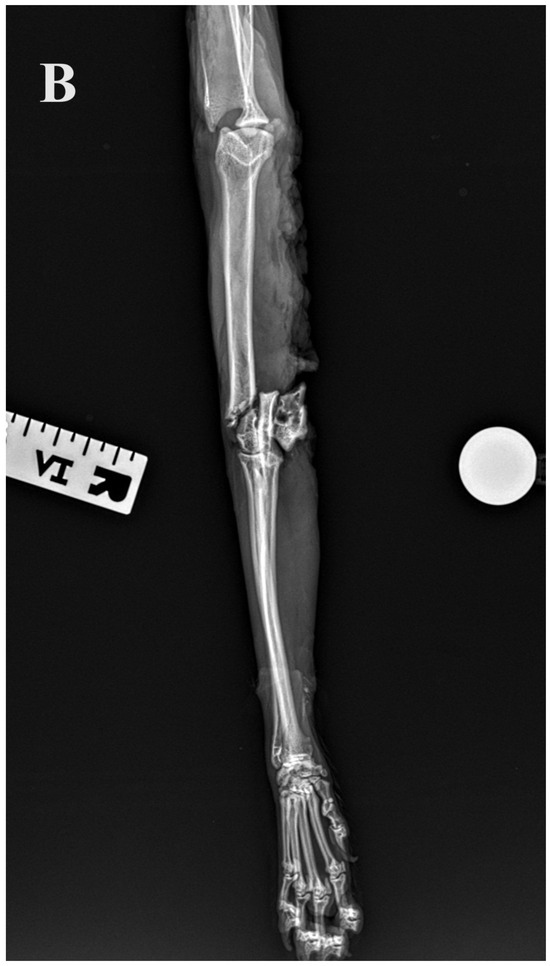

Figure 5.

(A,B) Initial lateral and cranio–caudal radiographs of the right forelimb of a female domestic cat show a displaced Y-T fracture. (C,D) Postoperative lateral and cranio–caudal radiographs show a small articular surface defect (<1 mm) of humeral condyle and adequate alignment, adjacency and apparatus (2.0/2.4/2.7 3D printed plate, 2.4/2.7 straight interlocking bone plate and screws).